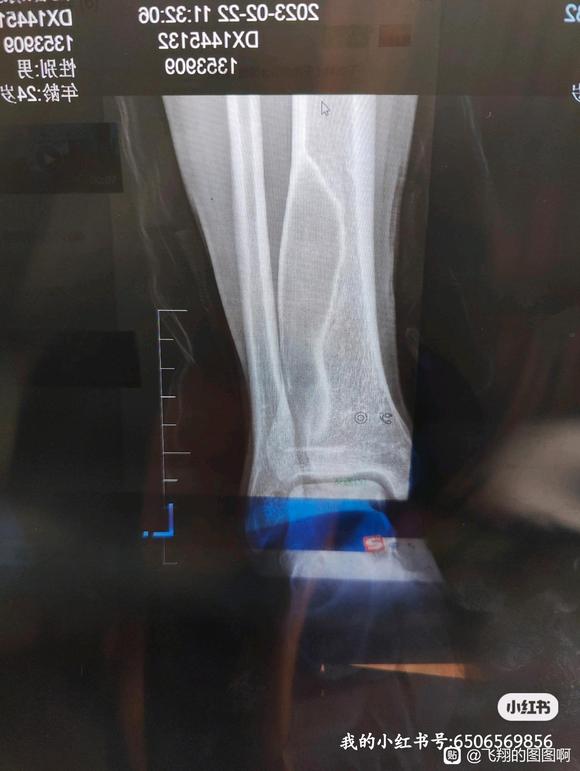

由于长期的不良习性,导致现在骨头都空了

医生说这是骨纤维异常增殖,就是原来是骨头的地方现在变成软组织了(息肉等)这种软组织没有硬度,不能支撑身体。由于小腿下侧骨头是支撑身体受力的,所以医生说我现在随时都有可能骨折。

而且,骨纤维异常增殖是全身范围的,目前西医方面的治疗方案只有做手术:在原来骨头空了的地方填医用骨水泥。

各种美好的事物都在离我而去,我以前虽然也知道,但是真正在医院看着自己骨头的CT时我才猛然意识到:原来我的症状已经如此严重了!